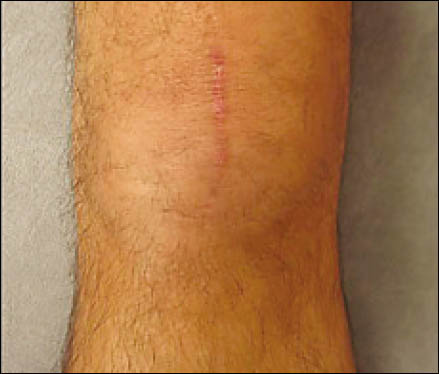

Se realiza un mini abordaje anterior de rodilla 2 cm proximal al polo inferior de la rótula y 3 cm distal al mismo, luego se realiza la esqueletización del polo patelar distal cruentándolo a la demanda. Mediante dicho gesto se reconoce la superficie ósea permitiendo la implantación precisa de los arpones, centralizándolos en plena masa esquelética, se colocan en forma paralela 2 anclajes óseos de 3.5 mm (Arthrex). (Fig. 3 y 4)

Figura 3: Visión intraoperatoria de la lesión del tendón patelar, colocación de 2 arpones paralelos